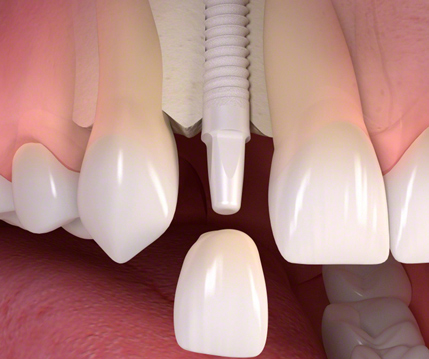

Implantologie

Mit Hilfe der Implantologie ist es möglich Zahnersatz in den verschiedenen Formen naturgetreu herzustellen. Implantate sind u.a. in der Lage einzelne Kronen, Brücken oder schleimhautgetragene Prothesen in der Mundhöhle zu verankern.

Dazu einige Anwendungsbeispiele: